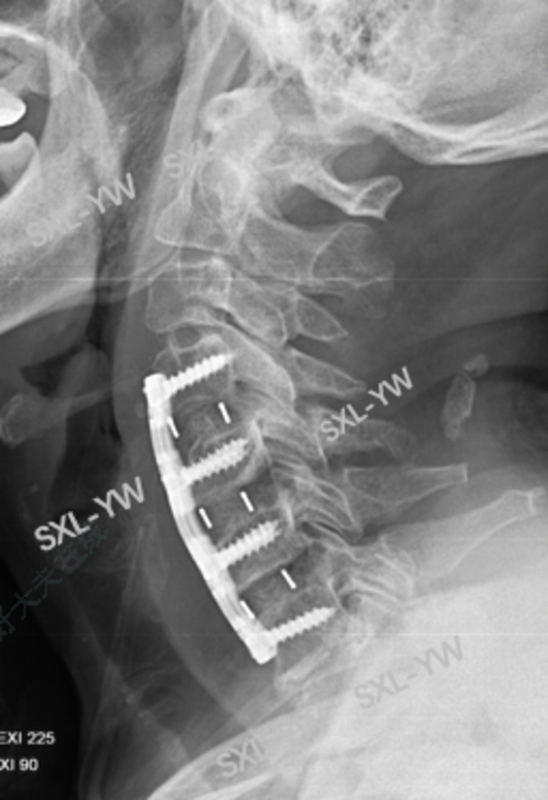

术后X线:颈椎曲度恢复生理前凸,椎间隙高度恢复正常,颈椎4/5不稳得以纠正。

术后CT:椎体后缘骨赘切除彻底,减压区很大,呈锥形。

手术时间2小时,术中出血75ml左右,术后第2天下地活动,术后第4天出院,患者术后神经功能恢复理想。